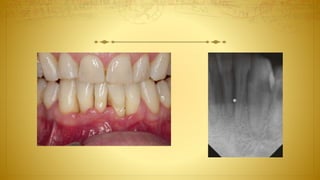

Radiographic

Assessment

 Periapical Radiograph

 Bitewing Radiograph

 Cone Beam Computed Tomography

 Panoramic Radiograph

Periapical Radiograph

Cone Beam Computed Tomography